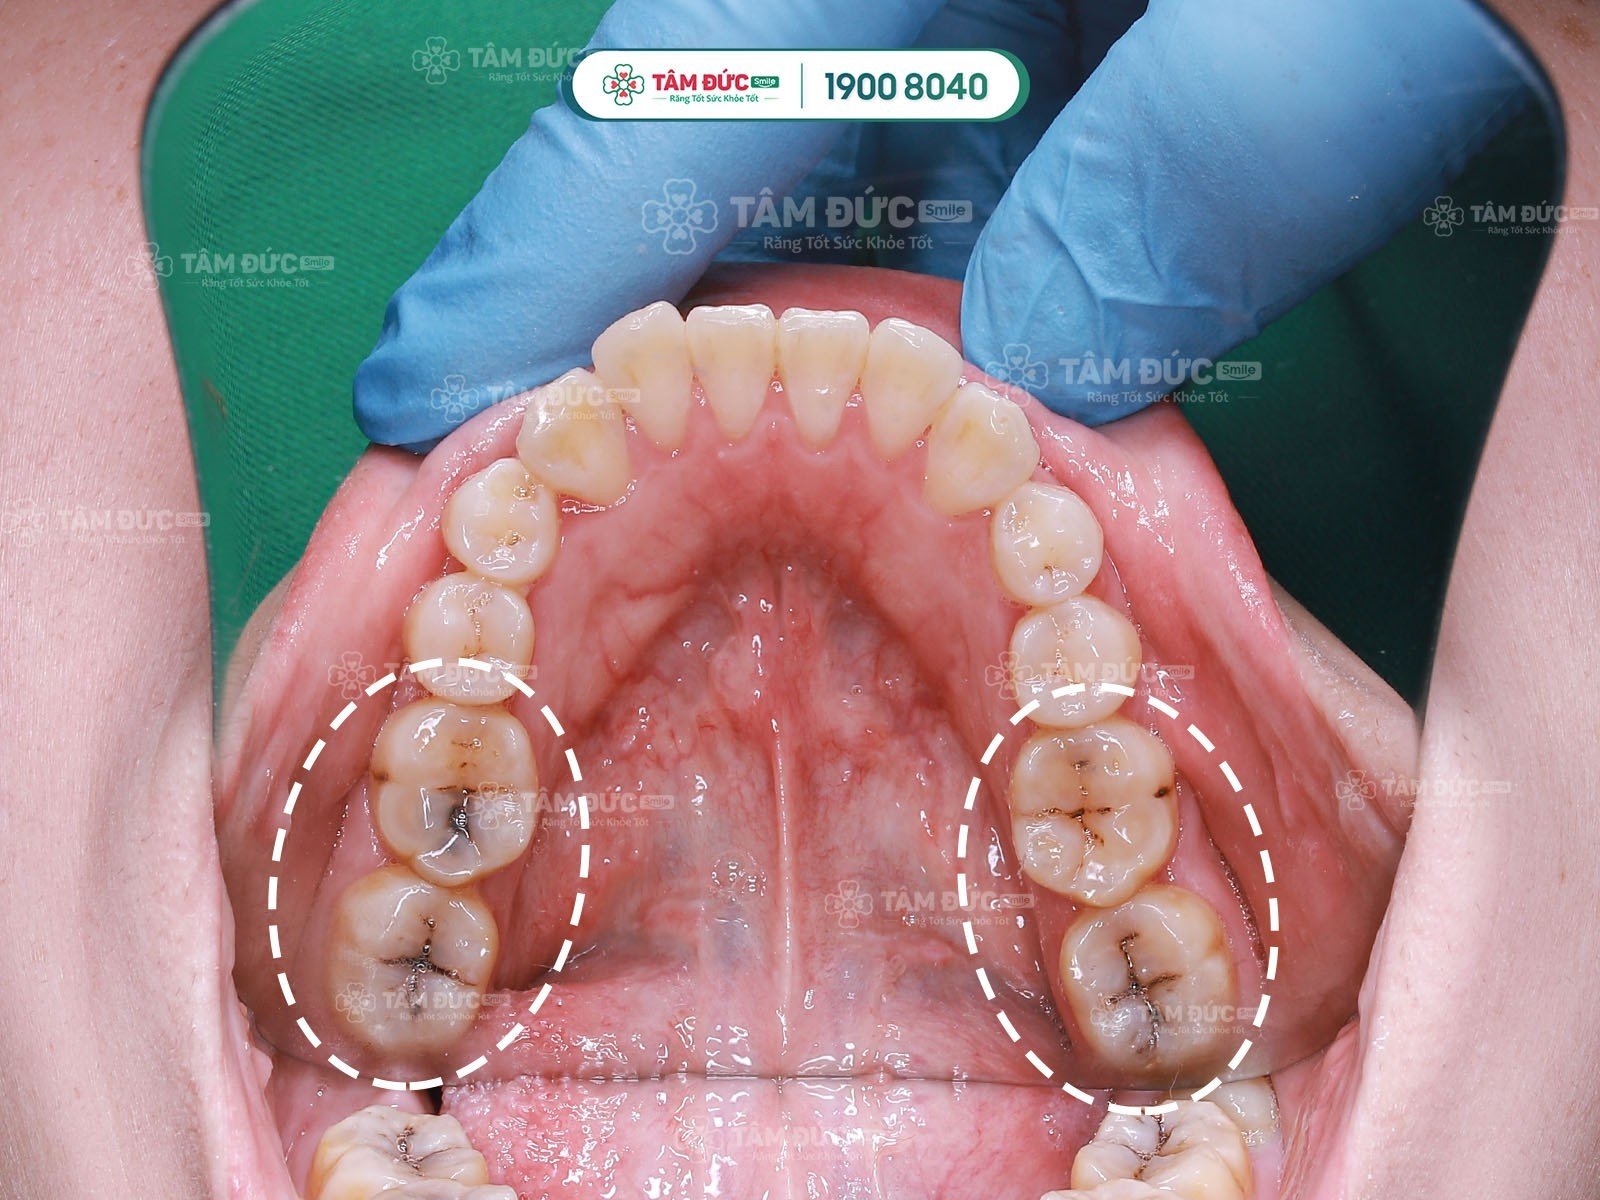

Các trường hợp răng cần chữa tuỷ